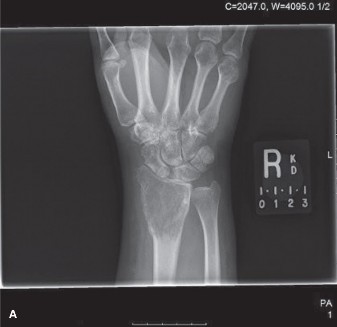

Radiographic Evaluation

Anteroposterior and lateral radiographs of the right knee demonstrated an eccentric, purely lytic lesion in the metadiaphyseal region of the distal femur, extending into the subchondral bone of the lateral femoral condyle. The lesion was expansile, with a narrow zone of transition, and showed no significant sclerotic rim, a classic radiographic hallmark of an active benign or low-grade malignant bone tumor. Cortical thinning and a pathological stress fracture line were noted along the lateral cortex. There was no evidence of periosteal reaction, Codman triangle, or internal matrix mineralization (no chondroid rings/arcs or osteoid cloudiness). The epiphyseal plate was noted to be completely fused, consistent with the patient's skeletal maturity.

Figure 1: Initial AP radiograph demonstrating an expansile lytic lesion in the distal femur, extending to the subchondral bone, with cortical thinning and lack of sclerotic margin.